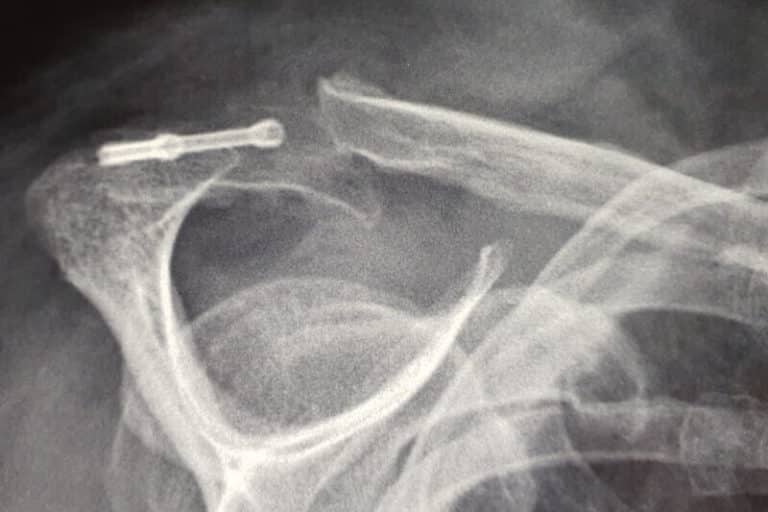

Dans l'anatomie de l'épaule, il existe deux zones particulièrement touchées par les accidents que sont la clavicule et l'articulation gléno-humérale.Dans tous les cas, la chirurgie de l'épaule y tient une place prépondérante L'une de ces causes peut être un os qui ressort de l'épaule, ce qui peut être extrêmement douloureux et limitant dans les mouvements du bras. L'acromion de l'épaule, qu'est-ce que c'est ? L'articulation de l'épaule est formée de l'omoplate (os plat du dos aussi nommé scapula), la clavicule (os reliant le sternum et le membre supérieur) et l'humérus (os long du bras).L'acromion est un bourrelet osseux de l'omoplate.

Anatomie de l'os d'épaule illustration stock. Illustration du humain 44177841. Description de l'anatomie d'une épaule : approches simplifiée et détaillée : la structure osseuse (clavicule, omoplate et humérus), les muscles (muscle deltoïde et muscles de la coiffe des rotateurs), les articulations (articulations gléno-humérale et acromio-claviculaire), les nerfs et artères (nerfs supra-scapulaire et thoracique long) C'est au niveau de l'acromion que se situe l'articulation de l'omoplate (voir sa situation anatomique) avec la clavicule.

Anatomie de l’épaule Chirurgie de l'épaule, du coude et du Sport. L' acromion est une apophyse osseuse (extrémité osseuse) de forme triangulaire et aplatie, prolongeant l'omoplate en haut et en dehors de l'épine scapulaire L'épaule est une des articulations les plus complexes du corps humain, permettant une grande amplitude de mouvement.